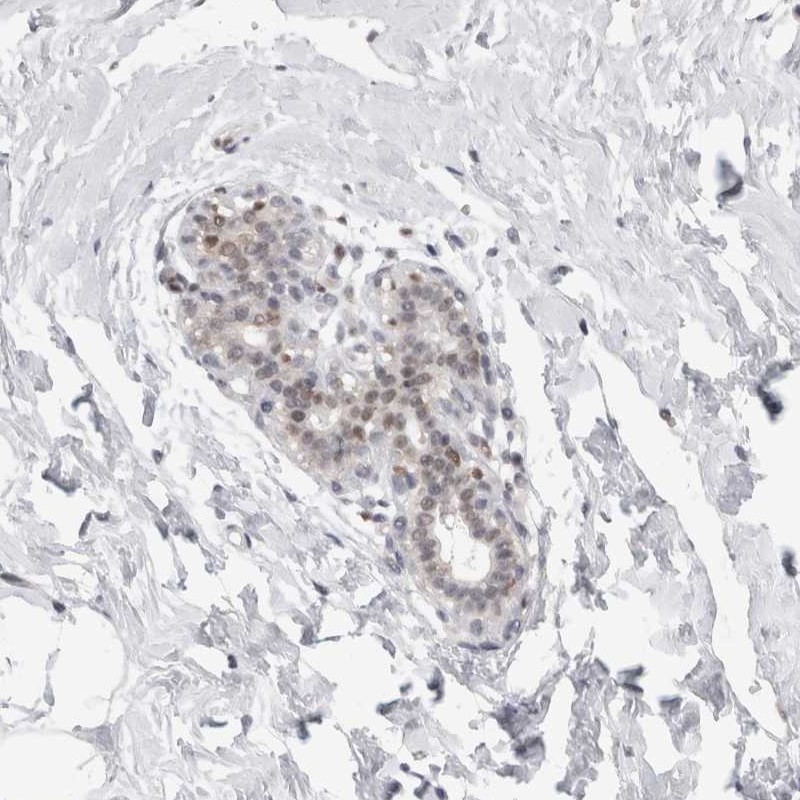

Immunohistochemical staining of human breast shows weak nuclear positivity in glandular cells.